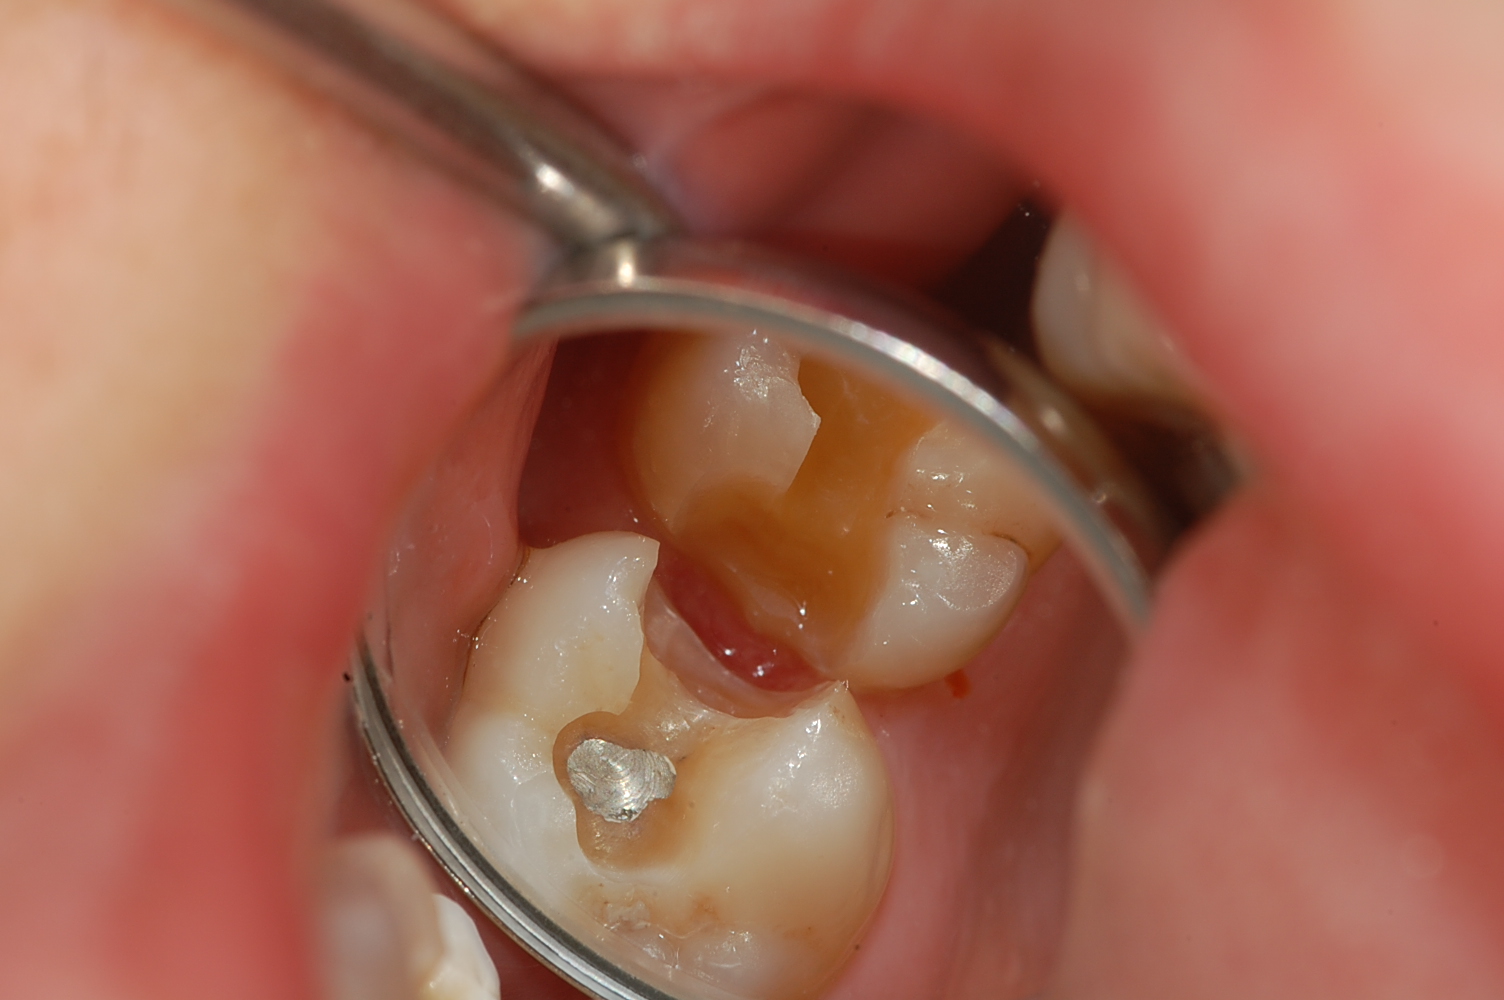

[보철,충치치료] 제목 : 상악 구치

인접면 충치, 골드 온레이